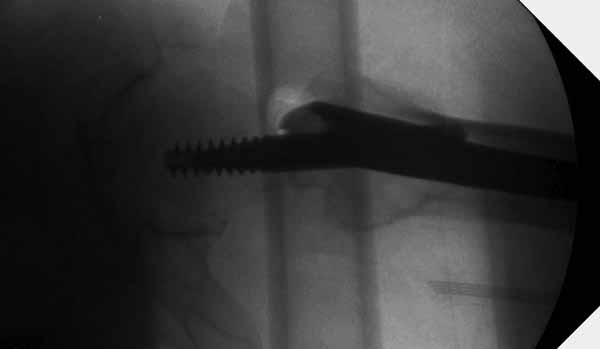

Вторая операция- это фаза сохранения головки бедра. Желательно приложить все усилия и сохранить головку, но, как видно, “фиаско” продолжается. Здесь вместо нейтрализации сил между медиальной и латеральными сторонами была попытка удержать варус. Варус не удержать ни деротационными шурупами о котором говорили и не костными стружками вбитые в шейку, потому что вся нагрузка упирается в головку.

Как отметил Евгений, 95 degree Blade Plate Fixed Angle device  расчитана на восстановление взаимоотношении между головкой и диафизом, а все остальные фиксаторы (Gamma, Afifuxus и др.) работают за счет нагрузки в верхнем полюсе головки. Верхний полюс успели разрушить, и в головке единственное место, который смог бы удержать широкий клинок конструкции, это медиально-низкий сегмент. После установки клинка засчет дистракции можно удлинить конечность на 15мм, а добавленный в дефект ауто-графт закончил бы дело.